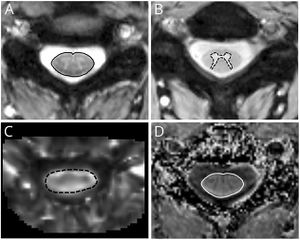

- 1.92 Quantitative Spinal Cord MRI in Radiologically Isolated Syndrome